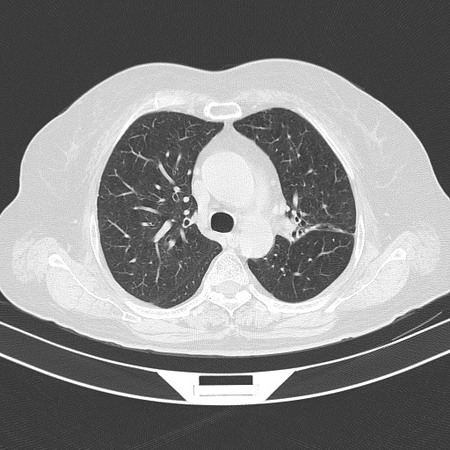

以下是引用sdzyy在2008-11-21 14:57:00的发言:[br]右肺结节影,建议定期复查!支扩,左侧叶间胸膜增厚.

以下是引用卜一在2008-11-21 14:40:00的发言:[br]炎性结节可能!建议定期复查!另:支气管扩张征伴感染!

以下是引用guanaishengming在2008-11-21 17:26:00的发言:[br]右肺结节影,建议定期复查!